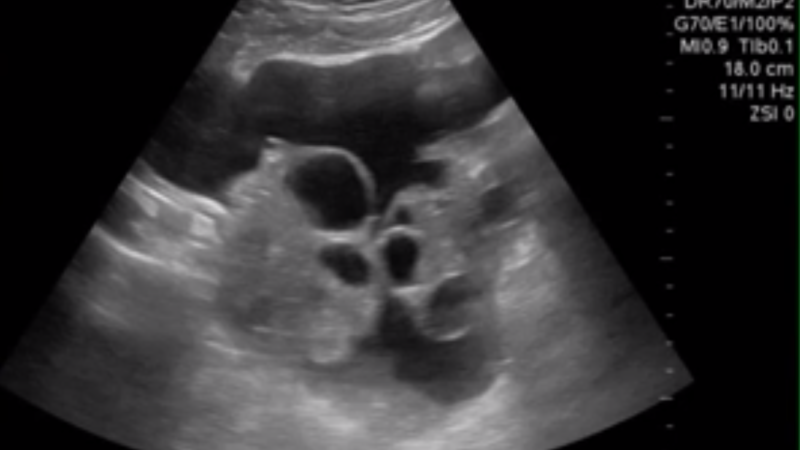

Navigating the world of fertility can feel like stepping into a maze filled with new terms, tests, and numbers that all seem critical—but maybe a little mysterious, too. One term that you’re likely to hear a lot is Antral Follicle…